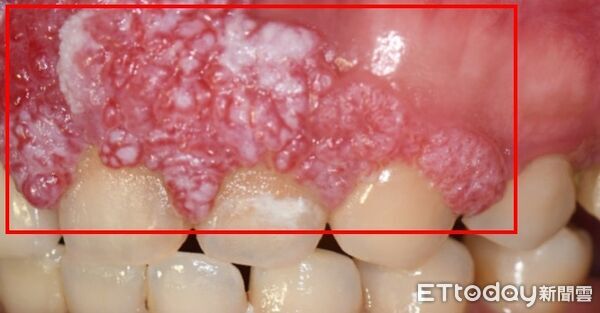

▲40歲許小姐無不良習慣,卻確診「上顎牙齦癌」,需大範圍切除上顎骨,還必須拔除鄰近腫瘤的10顆牙齒。(圖/中山附醫提供)

口腔癌長年被視為與抽菸、喝酒、嚼檳榔等習慣高度相關的疾病,但一名40歲的許小姐,生活作息正常且無任何不良習慣,卻在前年確診罹患「上顎牙齦癌」,不僅需大範圍切除上顎骨,還必須拔除鄰近腫瘤的10顆牙齒,身心承受巨大衝擊。